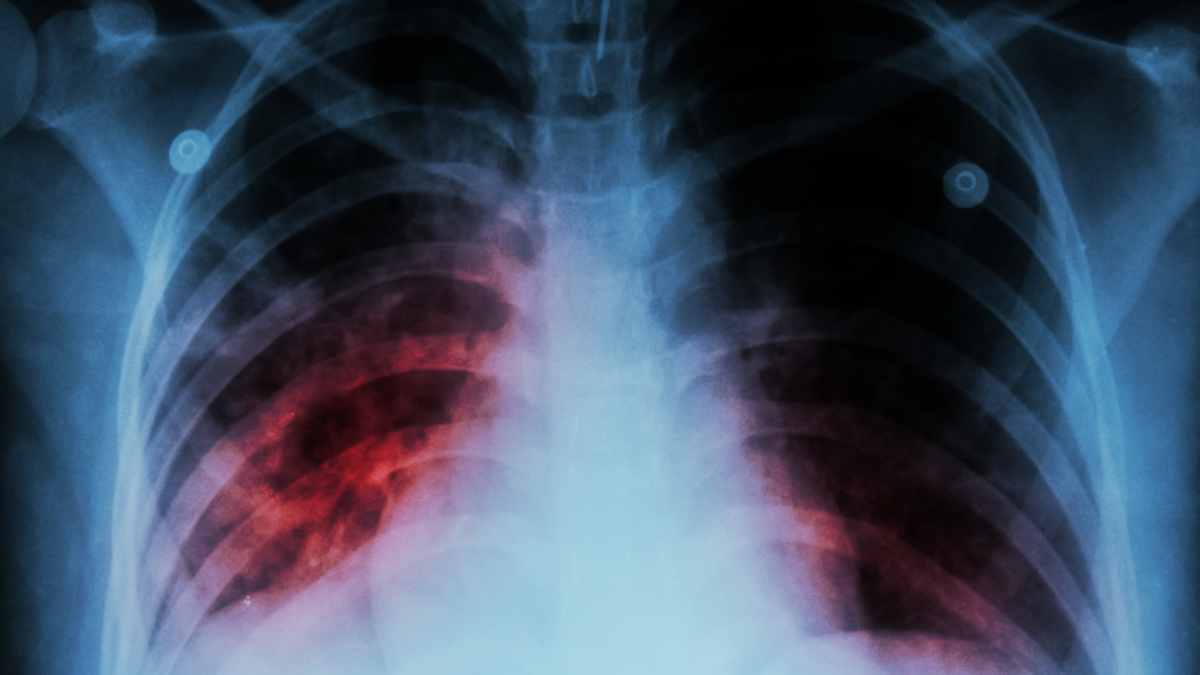

В прошлом году 198 детей и подростков заразились туберкулезом

В прошлом году 198 детей и подростков заразились туберкулезом.

«Elchi» сообщает, что об этом заявила директор Научно-исследовательского института легочных заболеваний Министерства здравоохранения Ирада Ахундова.

Она отметила, что на 2024 год этот показатель составил 278.

«Если в 2015 году показатель заболеваемости туберкулезом на 100 тысяч человек составлял 41,1, то в 2025 году эта цифра снизилась до 21,5. Примерно две трети больных туберкулезом составляют мужчины, а одну треть – женщины. Уровень выявления заболевания также значительно возрос. Так, если в 2015 году этот показатель составлял 53 процента, то в 2025 году он достиг 86 процентов», — сказала она.